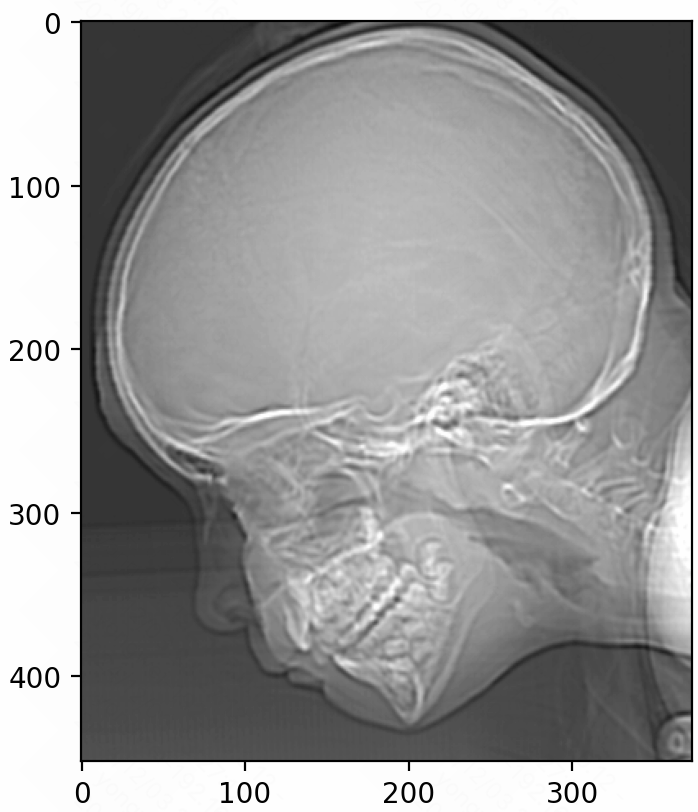

- Saturation and Noise

When an image is quantized, the continuous tonal range is mapped to a smaller set of discrete color levels. This can result in the amplification or accentuation of noise patterns, as the subtle variations in pixel values may be lost or masked by the discrete color levels.

In areas of the image with low contrast or subtle details, the quantization process can make noise more visible and pronounced, as the small variations in pixel values are more likely to be affected by the reduction in color levels.

1 | # The purpose of this code is to highlight the saturated pixels |